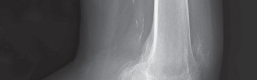

2. التصوير بالأشعة السينية (X-ray):

تُعد الأشعة السينية هي الأداة التشخيصية الأساسية لتقييم خشونة الركبة. يلتقط الأستاذ الدكتور هطيف صورًا للركبة من زوايا مختلفة، بما في ذلك صور الوقوف (Weight-bearing X-rays)، والتي تُظهر المفصل تحت تأثير وزن الجسم الطبيعي. تُظهر الأشعة السينية ما يلي:

- تضييق المسافة المفصلية: خاصة في الجانب الإنسي للركبة، مما يشير إلى تآكل الغضروف.

- تكون النتوءات العظمية (Osteophytes): وهي نتوءات عظمية صغيرة تتشكل حول حواف المفصل نتيجة للتآكل.

- تغيرات في كثافة العظام: مثل التصلب تحت الغضروفي (Subchondral Sclerosis).

- درجة الانحراف التقوسي: قياس الزوايا المحورية للساق لتحديد مدى التقوس بدقة.